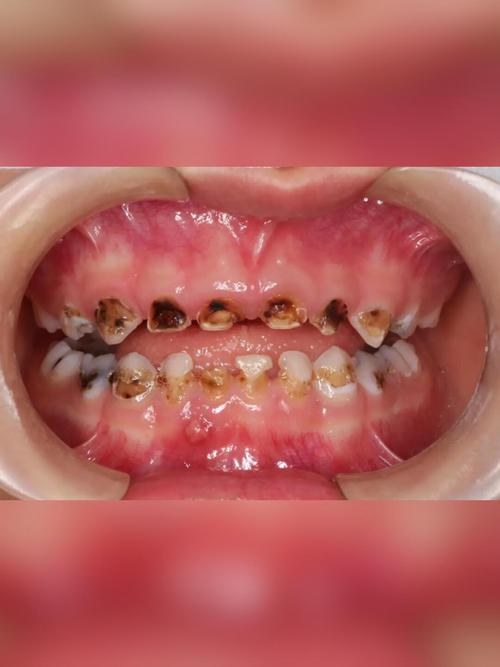

很多家长会认为:“反正乳牙要换,坏了就坏了,等恒牙长出来就好了。” 这是一个非常普遍且危险的误区。

乳牙有“虫窟窿”(也就是龋齿,俗称蛀牙)不治疗,会带来一系列严重的后果,远比您想象的要复杂。

- 一口发黑、有洞的牙齿会让孩子不敢笑、不敢说话,产生自卑心理,影响社交和心理健康。